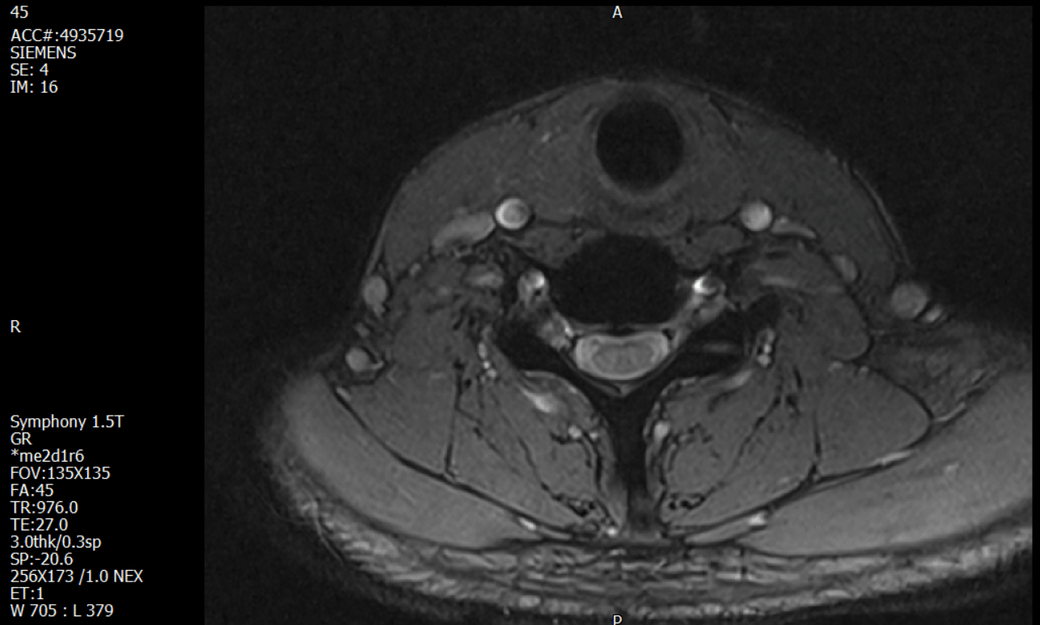

경추 요추 디스크 MRI판독 부탁드립니다.

- 3개월전 좌측 상지 저림(힘빠짐) 발생. 이틀뒤 에 좌측 하지 저림(힘빠짐) 발생.

(힘이 축처지는 느낌이라서 힘빠짐이라고 하지만, 실제 근력 문제, 감각이상, 활동 문제 없음)

-11월, 증상발생 직후 잠실소재 척추전문병원 MRI 요추경추 촬영 후 신경외과 박사 진료, 허리는 매우 건강, 경추는 퇴행성 진행되고 있지만 디스크라고 보기 어려움. 신경막만 살짝 건드리는 정도고 이 정도로 힘빠짐이나 저림이 오지 않고 원인은 다른 곳에 있을 가능성.

-12월, 분당서울대병원 재활의학과 진료, MRI 영상보고 딱히 다른 말은 없었음. 근전도 검사해보자 해서 신경전도, 근전도 검사 진행, 검사결과 이상없었고, 신경쪽 문제는 아예 배제해도 될것이라고 함. 정신쪽에 기인한 문제일 가능성 제시.

-올해 1월, 국립암센터 재활의학과 진료, 병명을 찾기가 쉽지 않을 것

-올해 1월, 분당서울대병원 신경과 진료, MRI영상보더니 디스크가 있고 저림과 힘빠짐이 이에 기인했을 가능성이 충분히 있다고함. (경추만 말한것인지 요추도 포함인지 모르겠으나 디스크 시술 방안을 제시함) , 팔다리가 우연이 동시에 저림이 올수 있는지에 대해서 물었더니 이틀 상간으로 발생했기 때문에 동시라고 보기 어렵다고함...

1. MRI 상 , 경추와 요추에 디스크가 있나요? 있다면 좌측 팔과 다리에 저림 및 힘빠짐을 줄 정도인가요?

2. 혹시 영상의 퀄리티가 떨어져서 의사끼리 의견이 다른것일까요? MRI는 1.5T로 촬영된 것인데, 3.0T로 재촬영할 필요가 있을까요?

3. 디스크로 인한 증상이라면, 목과 허리의 디스크가 이틀 상간으로 문제가 생길수 있나요?

특히나 요추MRI는 문제가 없다고 들었던 터라 다리저림은 어떻게 설명할수있는것인지 모르겠네요.

• 1. MRI 사진을 보았을 때 디스크를 의심해볼 수 있는 소견이 살짝살짝 보이긴 합니다만, 상하지의 저림 및 힘빠짐을 유발할 정도인지는 솔직히 회의적입니다.

2. 영상의 퀄리티는 나쁘지 않아 보입니다. 굳이 재촬영을 하실 필요는 없어 보입니다.

3. 개인적으로는 디스크로 인한 증상이 아닐 것으로 보나, 만약 디스크가 맞다면 우연하게 목과 허리 디스크 발병이 이틀 간격을 두고 나타났을 가능성을 생각해야 하는데, 현실적으로 그 가능성이 높지 않습니다.

4. 말씀하신 것처럼 특히 요추부 MRI는 디스크를 찾기 어렵습니다.

상기 MRI 소견으로는 심한 증상을 보일 정도는 아니며 디스크의 가능성은 적어보입니다.